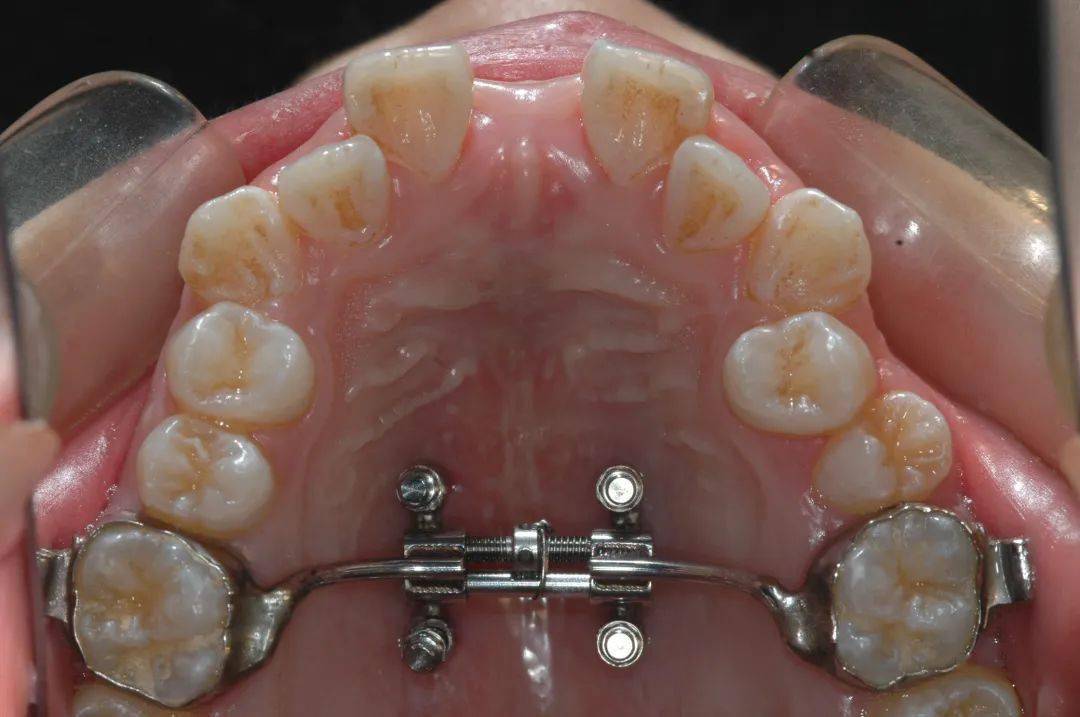

2013年贾海潮在美国加州大学洛杉矶分校做访问学者,正好有老师在做“种植钉辅助支抗扩弓”方面的研究——在上颌植入几颗小小的微螺钉,就可以直接在骨头上施力“扩弓”。以往需要外科手术才能解决的问题,在牙椅上就能实现,贾海潮觉得这个方法对临床很有用。

学到了这个“对临床很有用”的技术,贾海潮回到祖国。2014年国内还没有这方面的器械,他和技工中心的技师合作定制,开始进行探索研究。

随着国际学术交往和技术的进步,2017年起“种植钉辅助支抗扩弓”相关的材料、器械被引入国内,逐渐为广大正畸医生了解、掌握,临床应用也越来越广泛。特别是近年来,“种植钉辅助支抗扩弓”方面的研究逐渐成为国际正畸学研究的热点之一。2018年,贾海潮获得2项实用新型专利。

2021年,贾海潮以第一作者和通讯作者的身份,在该期刊发表了研究论文,采用随机对照试验,揭示了种植钉辅助上颌快速扩弓治疗效果更好,副作用更小,是生长发育后期更好的扩弓方法。

讲起临床研究,贾海潮如数家珍。60例随机对照试验,在口腔正畸临床研究中无疑是一个大样本研究,30例使用种植钉辅助上颌快速扩弓,30例采用传统的牙支抗扩弓,长达4年多的病例收集,每一个病例都亲自测量、亲自记录。正是这样扎实的临床研究,赢得了国际评委们的认可。

十年来,贾海潮已累计完成种植钉辅助支抗扩弓300余例,年龄最大的患者42岁,以往需要外科手术才能解决的问题,通过4个直径不到2毫米的微螺钉就能解决,对于医生和患者都是更好的选择。